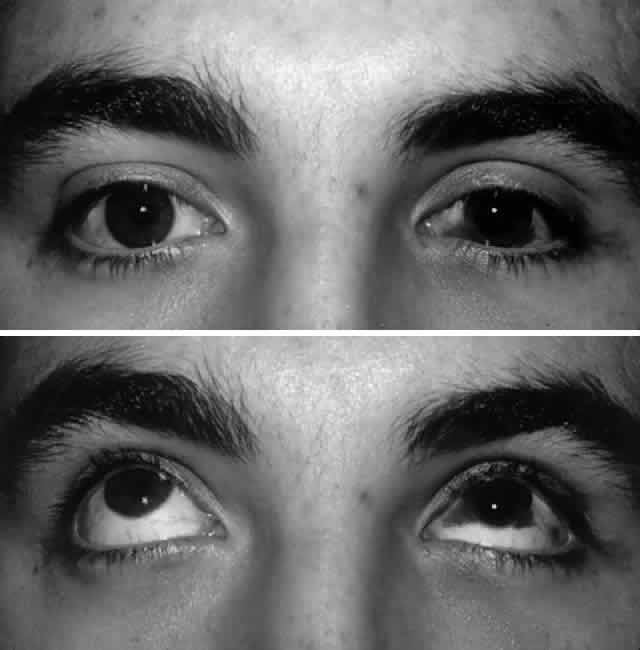

and elevate the prolapsed tissues.  Fig. 5. Orbital floor blow-out fracture repair via a transconjunctival approach

with lateral cantholysis. A. The periosteum is incised and then blunt dissection used to expose the

fracture site, thus releasing all entrapped orbital soft tissues. B. After the 360° perimeter of fracture is exposed and all prolapsed

tissue placed back in the orbit, the orbital implant is placed. In this

case, a porous polyethylene sheet was used to cover the defect and was

secured with two microscrews. Fig. 5. Orbital floor blow-out fracture repair via a transconjunctival approach

with lateral cantholysis. A. The periosteum is incised and then blunt dissection used to expose the

fracture site, thus releasing all entrapped orbital soft tissues. B. After the 360° perimeter of fracture is exposed and all prolapsed

tissue placed back in the orbit, the orbital implant is placed. In this

case, a porous polyethylene sheet was used to cover the defect and was

secured with two microscrews.

of edema (Fig. 7).  Fig. 7. A. Postoperative appearance of patient in Figure 3 one month after left orbital blow-out fracture repair. B. Note good globe position with no evidence of enophthalmos. Ocular motility

returned to normal. Fig. 7. A. Postoperative appearance of patient in Figure 3 one month after left orbital blow-out fracture repair. B. Note good globe position with no evidence of enophthalmos. Ocular motility

returned to normal.